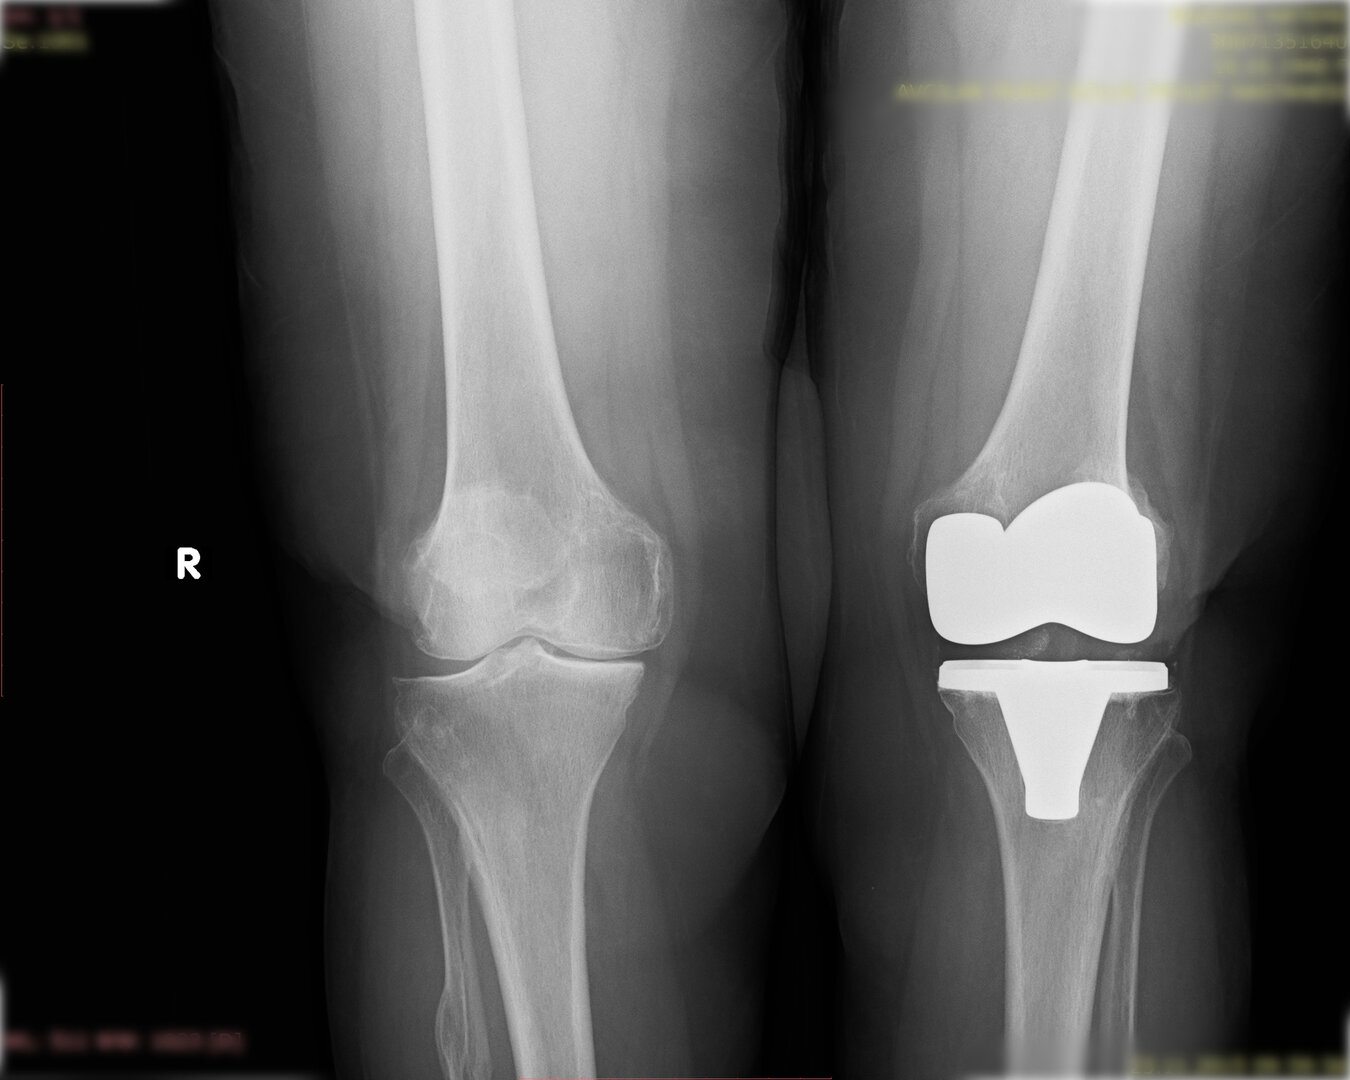

Aşınmış, hasar görmüş ya da eklem yüzeyleri tamamen bozulmuş diz ekleminin, yapay bir eklemle değiştirme işlemidir. Ameliyatta, ağrıya neden olan hasarlı kemik ve kıkırdak dokular çıkarılarak; yerine metal ve özel plastikten yapılmış, uzun ömürlü bir protez yerleştirilir. Bu sayede diz, tekrar ağrısız ve stabil bir şekilde çalışır hale gelir.

Peki kimlere yapılır? Genellikle osteoartrit (eklem kireci) ilerlemiş, ağrı ilaçlarla ya da enjeksiyonlarla geçmeyen, fizik tedavisi yeterli kalmayan kişiler bu ameliyat için adaydır. Tabii karar; MRI, röntgen, muayene ve doktor-hasta görüşmesiyle birlikte verilir.

Gonartroz (diz eklemi kireçlenmesi) tedavisinde protez cerrahisi öncesinde bir takım tedaviler uygulanmaktadır.

Artık hastanın ağrılarının artması, 100 metre bile yol yürüyememesi, istirahat ve ağrı kesicilere rağmen ağrılarının devam etmesi durumunda total diz protezi ameliyatı planlamaktayız. Bu ameliyat için önemli bir kriter de hastanın yaşıdır. Genç hastada özellikli bir durum olmadıkça tercih ettiğimiz bir tedavi yöntemi değildir.

Peki total diz protezinde ne yapıyoruz?

Eklem yüzeyleri özel kılavuzlar yardımı ile temizlendikten sonra metal protez eklem yüzeylerine bir kemik çimentosu ile adapte diyoruz. Bu iki metal yüzeyin sürtünmesini azaltmak için polietilenden yapılmış özel bir plastik tabakayı sisteme dahil ediyoruz.

Büyütmek için üzerine tıklayınız.